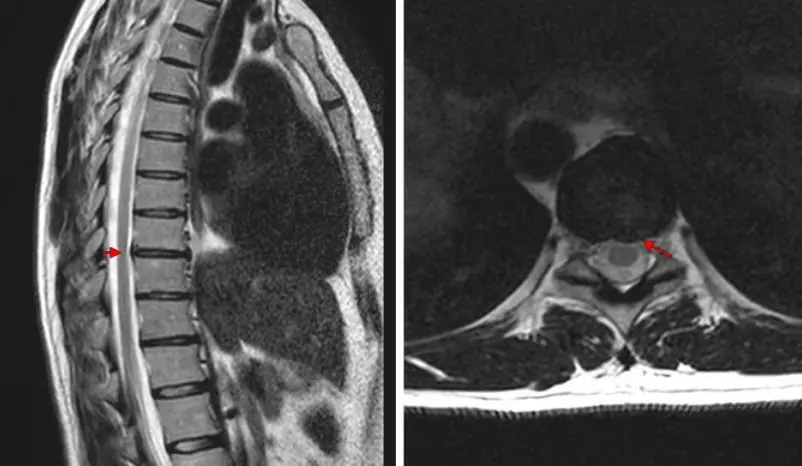

Un ECG a montré que tout allait bien au niveau du cœur. À l'hôpital, j'ai subi un examen complet et j'ai découvert que J'ai une ostéochondrose thoracique. Je ne m'attendais pas à ça ! Je fais du sport, je vais au yoga et je dors sur un matelas orthopédique. Tout cela en vain...

Rentgen